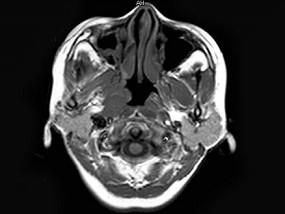

问题 女,34岁。右侧听力下降,耳鸣2个月。MRI平扫及增强扫描如图示,最可能的诊断是 ( )

选项 A、动脉瘤 B、未见异常 C、脑膜瘤 D、神经源性肿瘤 E、鼻咽癌

答案 E